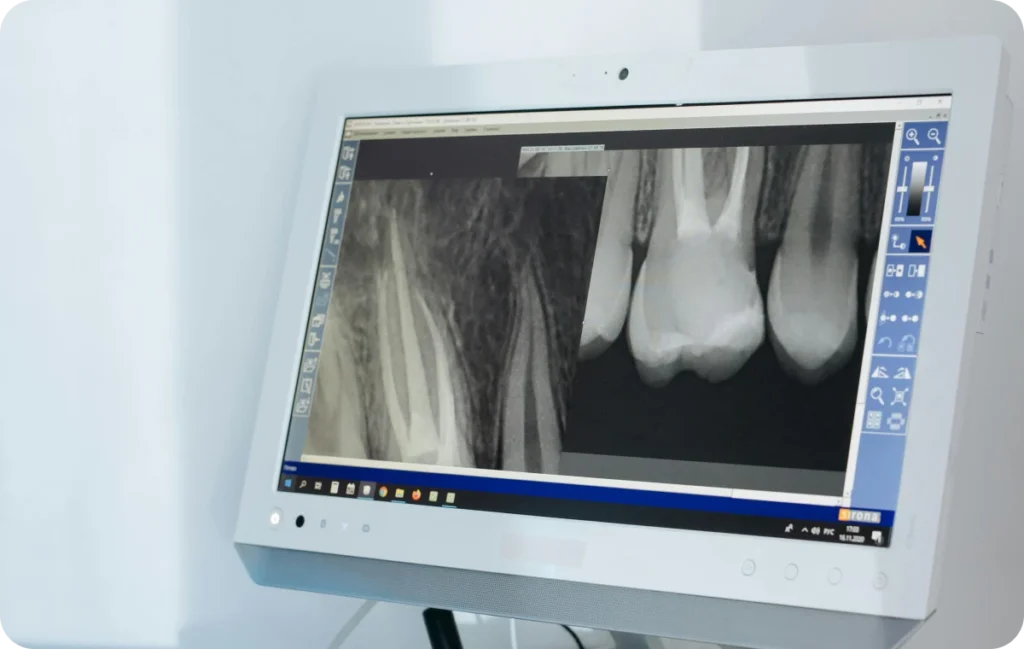

La première phase consiste en un diagnostic approfondi. Le dentiste réalise un examen clinique et procède à des radiographies. Ces investigations confirment l’atteinte pulpaire et évaluent la position des canaux. Ensuite, le praticien planifie la stratégie de traitement. Des dispositifs de haute précision sont mobilisés pour analyser la structure interne de la dent. Par ailleurs, une anesthésie locale est instaurée. Ce geste garantit un confort maximal durant l’intervention. La préparation minutieuse du patient et la vérification des indicateurs cliniques favorisent le succès de l’intervention.

Les procédures actuelles reposent sur des techniques innovantes, sans excès promotionnel, qui optimisent la prise en charge. D’une part, l’utilisation d’instruments rotatifs assure une intervention précise. D’autre part, l’imagerie numérique facilite la visualisation de la structure interne. Ainsi, le dentiste peut adapter chaque geste à la morphologie dentaire. Ensuite, la méthode de désinfection intègre plusieurs irrigations contrôlées. Par ailleurs, l’optique permet de mieux appréhender les nuances du traitement et de réduire les risques d’erreur. Ces approches permettent d’obtenir des résultats satisfaisants tout en respectant la dent naturelle.